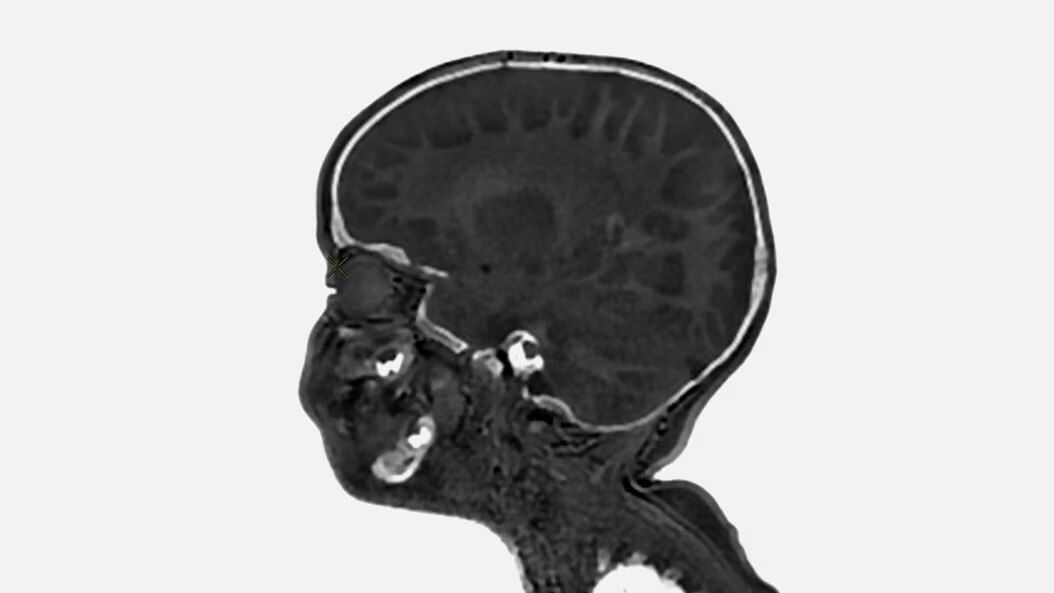

Pediatric MRI for SIGNA

Discover specialized pediatric MRI designed for your smallest patients. Ensure ease of use for technologists and clinical excellence for pediatric clinicians with pediatric MRI for SIGNA